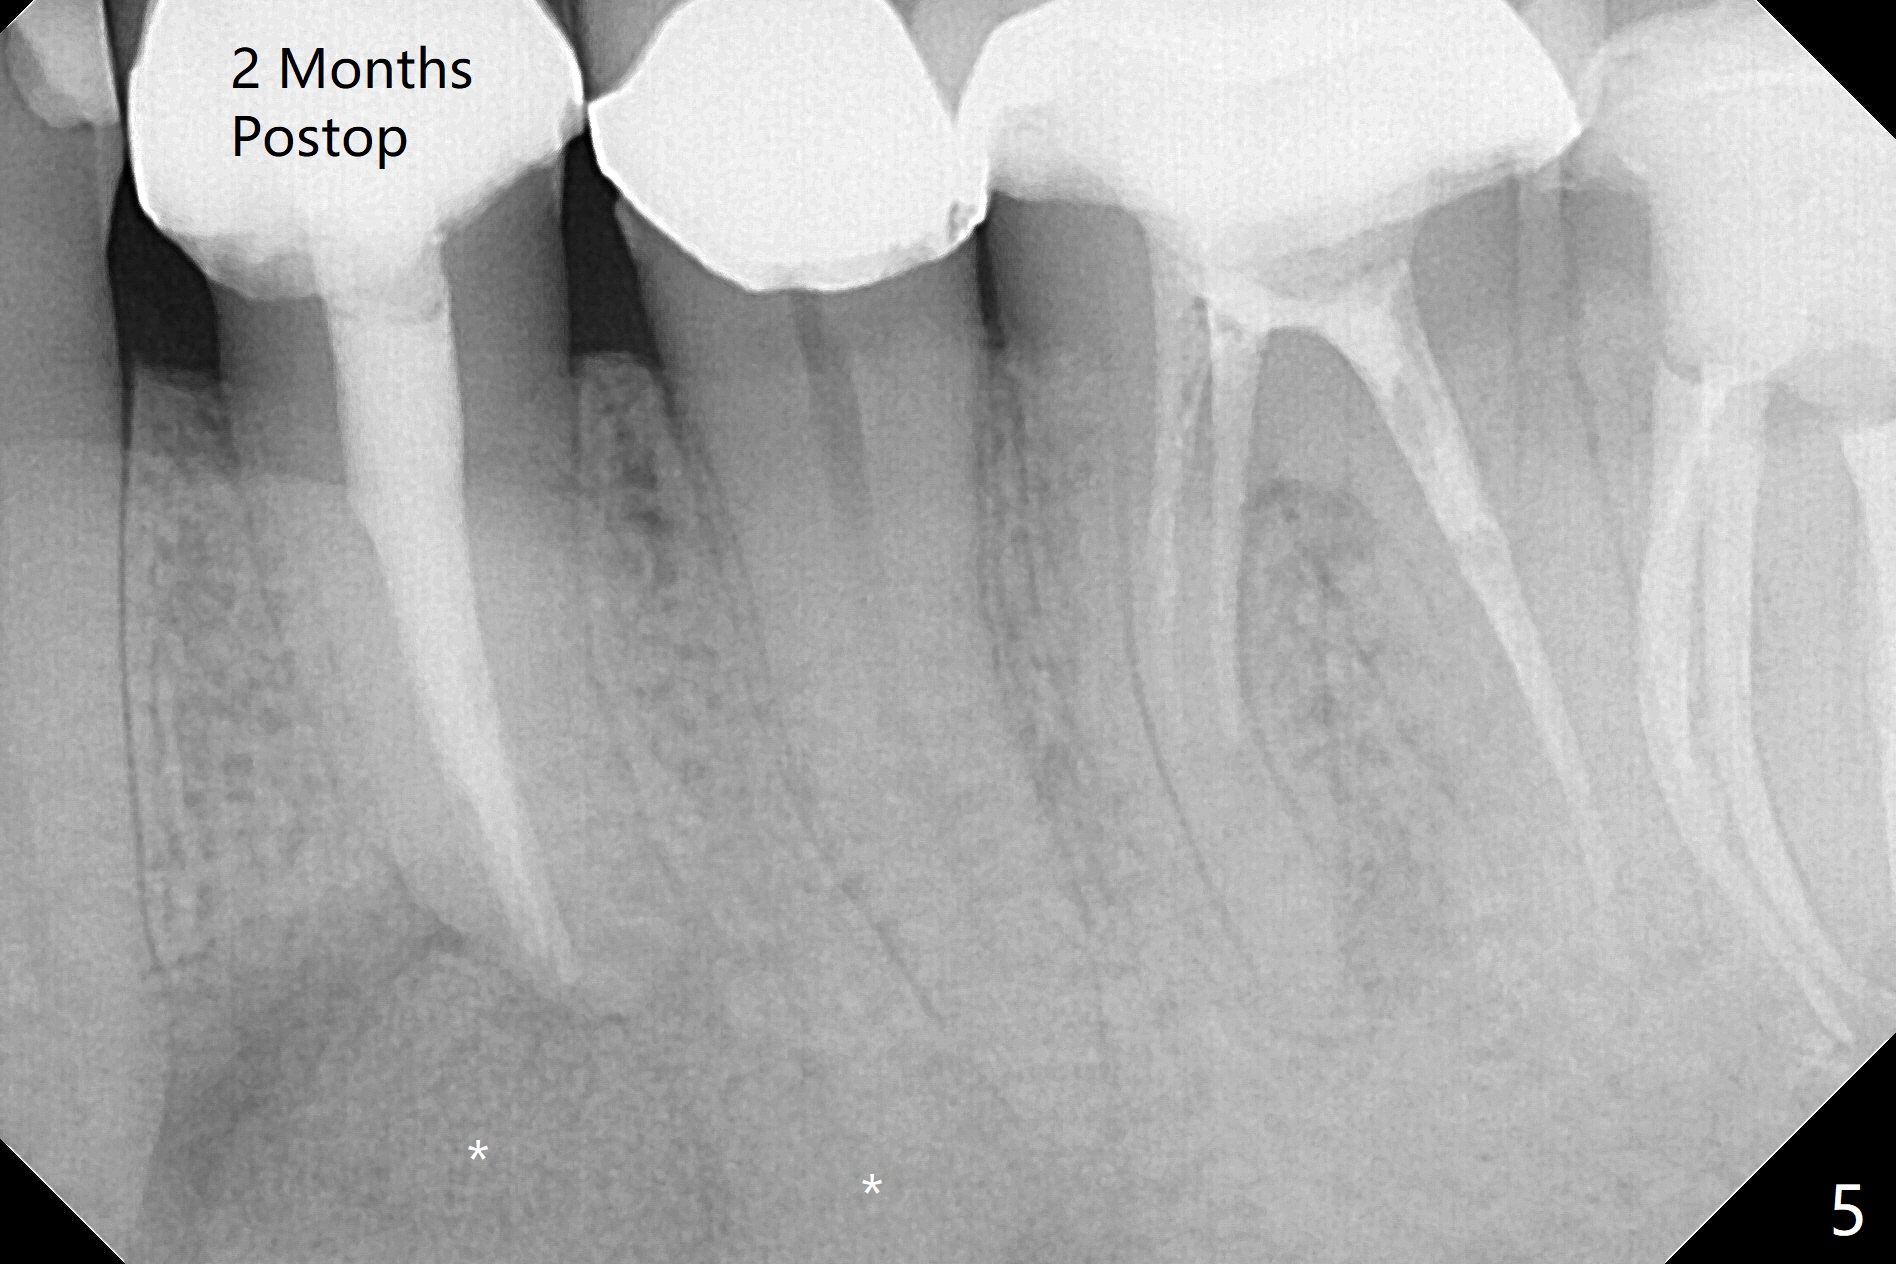

术前冷和电牙髓活力测定显示左下3活髓,不得不做一个长切口和附加切口(图二:>),在暴露颏神经后,在4根尖做囊肿切除术(图一),好像上颌窦外提升,使用上颌窦提升术器械才把囊肿挖出来,不同之处是颊侧骨壁特别厚,为了容易去除4根尖舌侧囊肿,做了根切(图三:<,与图三 ' (术前)对比),但是没做倒充,觉得根管充填完整。并且填入不少粘性骨块(图三)。病理报告:Left Mandibular Body, #21, Excisional Biopsy: Benign fibrous and granulation tissue with acute and chronic inflammation, consistent with periapical granuloma. Negative for odontogenic keratocyst and unicystic ameloblastoma. 左下颌骨体部,21号牙,切除性活检:良性纤维和肉芽组织伴有急性和慢性炎症,与根尖周围肉芽肿一致。牙源性角化囊肿和单房性造釉细胞阴性。术后两个月伤口愈合(图四),骨粉好像安居乐业(图五:*)。